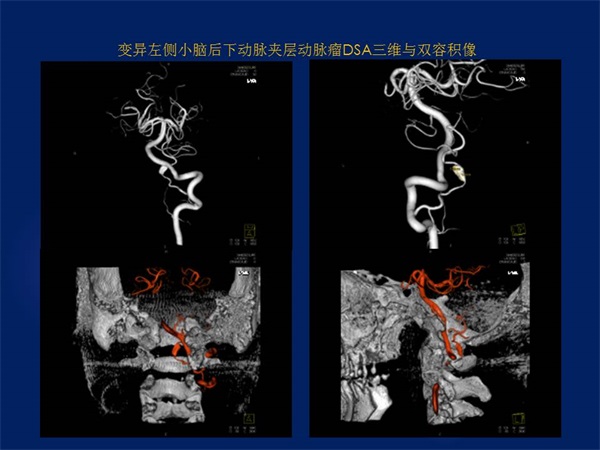

《三维影像融合技术在神经系统疾病诊治与研究中的应用》